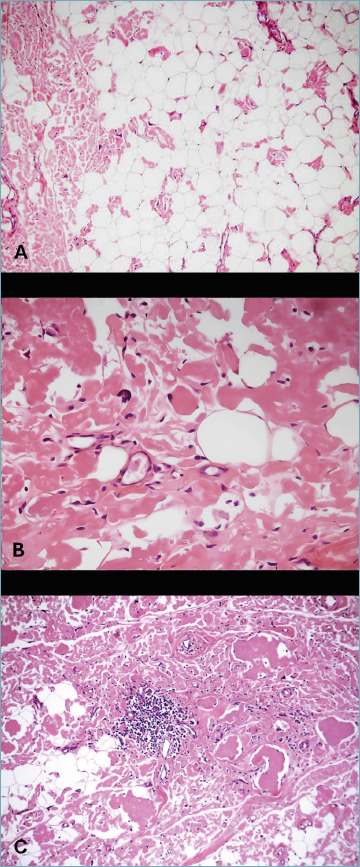

Introduction: The term amyloidoma applies to localized deposits of amyloid in the absence of systemic amyloidosis. Skeletal and soft tissue amyloidomas are very rare and the pathogenesis is usually associated with lymphoproliferative disorders (plasmacytomas or plasmacytoid lymphomas) or as a consequence of local chronic inflammation.

Methods: In this paper we report the histological and immunohistochemical features of four cases of musculoskeletal amyloidoma in association with combined laser capture microdissection (LCM) of Congo Red positive regions with a recent microproteomics workflow that improves the sensitivity of the analysis in order to confirm the nature of the protein deposit.

Results: Proteomic techniques allowed to elucidate the nature of the amyloid protein deposit, improving the results obtained by immunohistochemistry (IHC). IHC results were confirmed in two cases while LCM coupled with bottom-up microproteomics was necessary to type the other two cases, for which IHC was inconclusive.